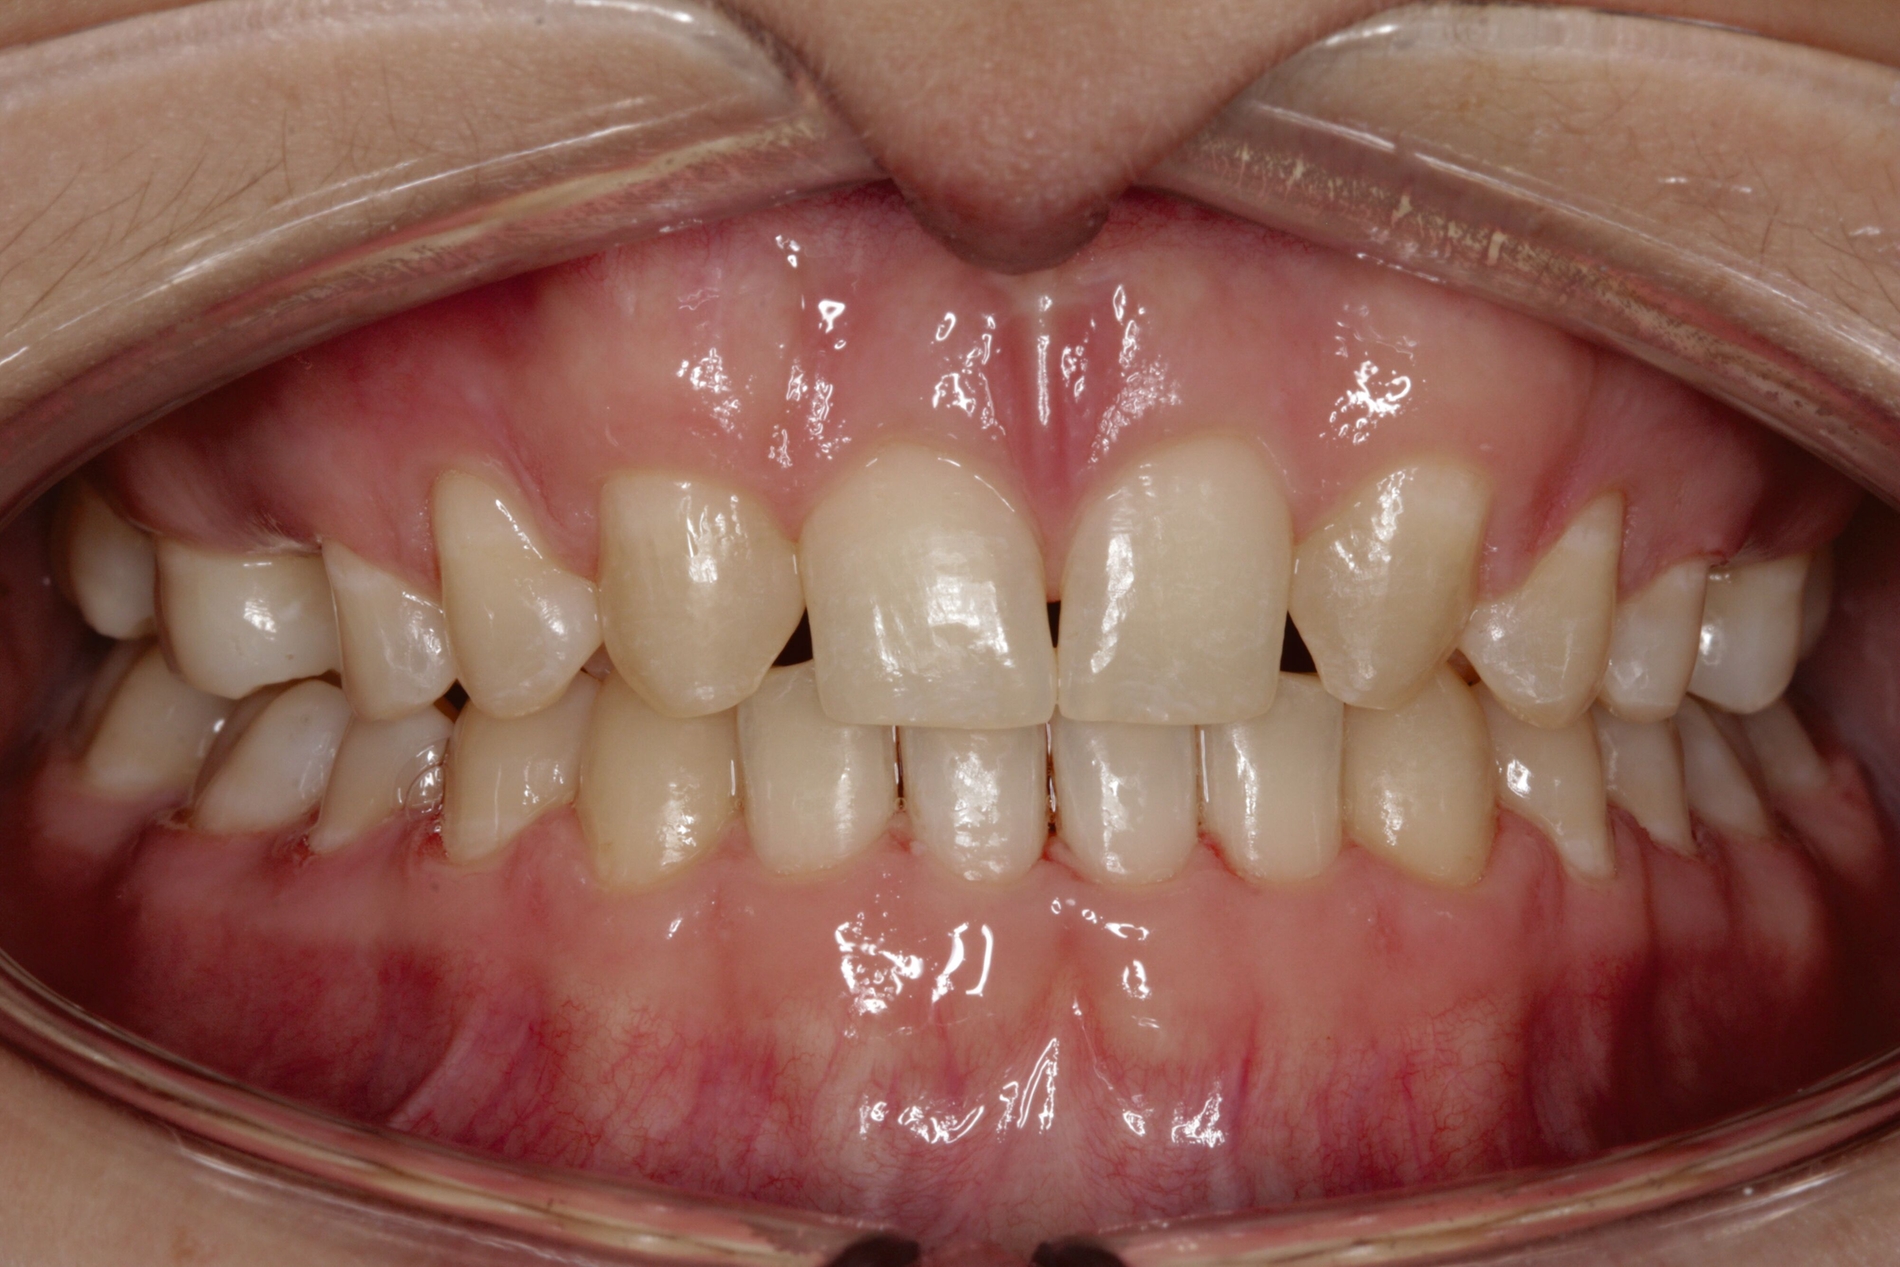

Bei dem gut zwölfjährigen Mädchen sind die seitlichen oberen Schneidezähne (Zähne 12 und 22) nicht angelegt. Zusätzlich zeigten sich verlagerte zweite obere Prämolaren.

Im vorliegenden Fall stand der Zahn 23 bereits im Mesialstand bei hoher Lachlinie und tendenziell konkavem Lippenprofil. Bezüglich Morphologie und Farbe waren die Zähne 13 und 23 nicht ausgeprägt eckzahntypisch. Es bestand kein Platzmangel im Gegenkiefer. Die Patientin war bei der Erstdiagnose 12,5 Jahre alt und im Wechselgebiss der zweiten Phase mit atypischer Durchbruchreihenfolge. Es bestand eine geringfügige Klasse II. Der Overjet war vergrößert bei vertikaler Wachstumstendenz, der Overbite war um circa einen Millimeter vergrößert aufgrund der geringfügigen Steilstellung der Oberkiefer-Front. Es bestand der Verdacht auf Nichtanlage der Weisheitszähne, 15 und 25 waren verlagert.